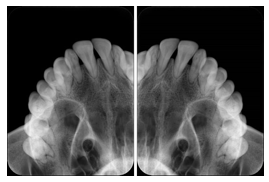

OO.1.2 Ophthalmology

1. A patient in rural Canada visits a general ophthalmologist and is found to have diabetic macular edema. The general ophthalmologist would like to discuss the case with a retina specialist before performing laser surgery. A fluorescein angiogram is done with multiple retinal images taken in a timed series after an intravenous injection. The images along with a Structured Display are shared via a Health Information Exchange with a retina specialist in Calgary, who opens them using his Ophthalmology EMR software and consults via phone with the general ophthalmologist. Both physicians view the images in the same layout so the retina specialist can provide accurate guidance for treating the patient.

2. A patient in rural Iowa visits his primary care physician for management of diabetes. Three non-mydriatic (patient's eyes are not dilated) photographs are taken of the back of each eye, and forwarded electronically along with a Structured Display to an ophthalmologist in Iowa City. The ophthalmologist reads the photos in an agreed upon layout so there is no mistake about what portion of which eye is being viewed. The ophthalmologist is able to tell the primary care physician that his patient does not need to come to Iowa City for face to face ophthalmologic care, but that there is a particular view of the left eye that should be photographed again in 6 months.

Ophthalmic Retinal Study Structured Display

Figure OO-3. Ophthalmic Retinal Study Structured Display